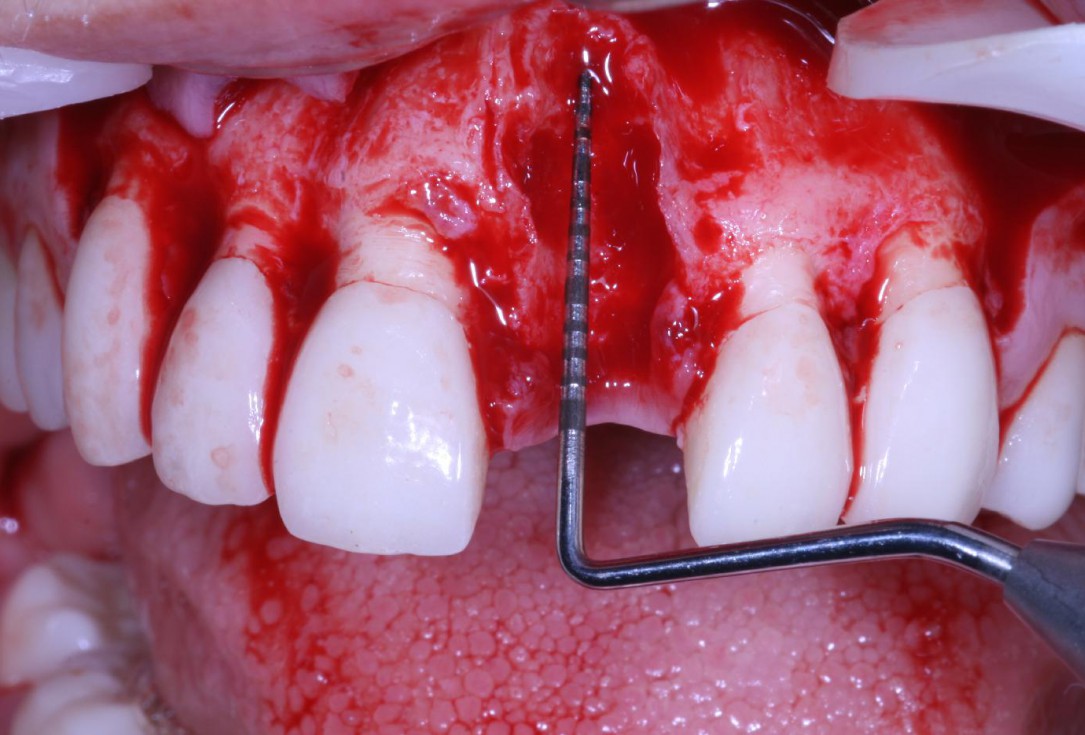

Mucosal thickening around bone level implants - Dr. A. Puisys

Full-thickness flap preparation bucally and lingually